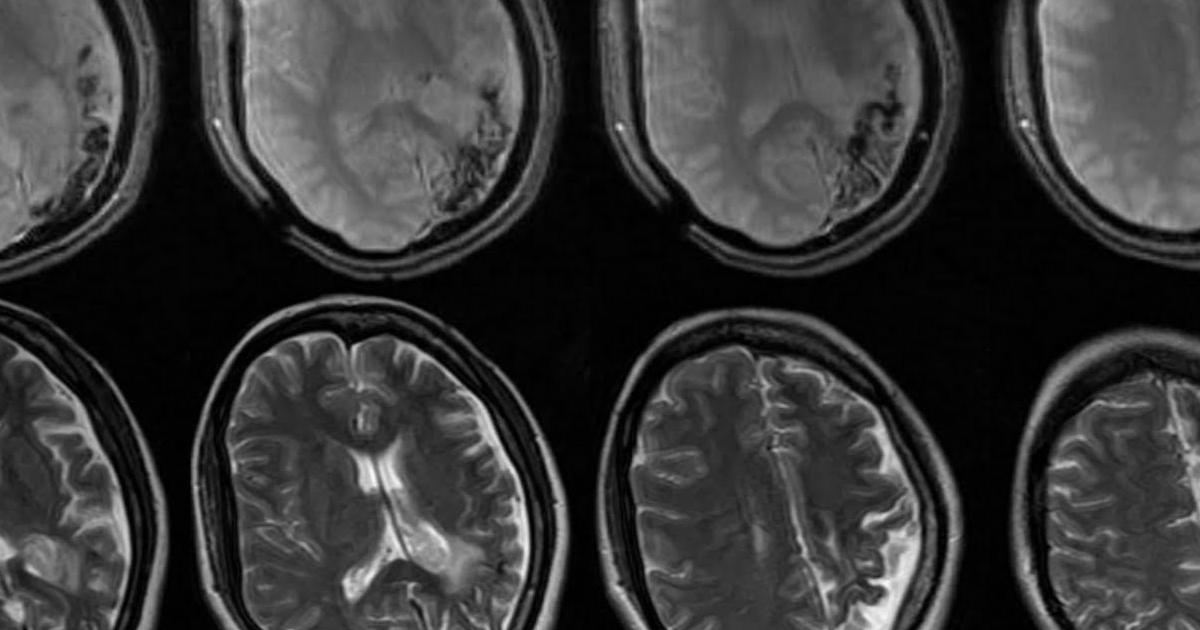

Angiomyolipoma is strongly associated with tuberous sclerosis, a genetic disease in which most individuals develop angiomyolipomas on one or both kidneys. This genetic disorder is rare and affects multiple bodily systems, causing benign tumors to develop in vital organs such as the brain, eyes, lungs, and kidneys. It can also cause other symptoms such as behavioral issues, developmental delay, intellectual delay, kidney disease, and skin abnormalities. More than fifty percent of patients with tuberous sclerosis (TS) also develop angiomyolipoma.

Neurofibromatosis (NF) is an uncommon condition that causes tumors to develop in the nervous system, including the spinal cord, brain, and nerves. The disorder is a group of three conditions: NF1, NF2, and schwannomatosis. NF1 causes symptoms such as tiny bumps within the nerves, freckles on the groin and armpit, brown spots on the skin, and scoliosis. NF2 can cause hearing loss, early cataracts, balance issues, and muscle wasting. Schwannomatosis is a separate form of the disease that leads to cutaneous schwannomas or benign central nervous system tumors.

Sturge-Weber Syndrome or SWS is a rare neurological disorder that causes a hallmark port-wine stain on the forehead and eyelid that is usually apparent at birth. Not all children with a port-wine stain have SWS, but all patients with SWS have the hallmark port-wine stain. The disorder can also cause abnormal blood vessels, intellectual delay, cerebral malformation, seizures, and glaucoma. SWS typically occurs sporadically with no known hereditary cause.